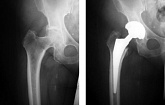

Hüftendoprothetik

In den späten Stadien der Arthrose des Hüftgelenks, mediale Frakturen des Schenkelhalses in der älteren Altersgruppe, ist die einzige Möglichkeit, sich zu erholen, das betroffene Gelenk durch eine künstliche Gelenkarthroplastik zu ersetzen.

Diese Methode ermöglicht es Ihnen, die Gliedmaße, das volle Volumen der Bewegungen im betroffenen Gelenk, zurückzugeben, um von ständigem Schmerz und Knirschen während der Bewegungen zu sparen und folglich den Patienten zu einem vollen aktiven Leben zurückzubringen.

Im Folgenden werden Röntgenaufnahmen und Fotografien vorgestellt, die das Ausmaß der Bewegung im betroffenen Gelenk vor und nach der Operation zeigen.